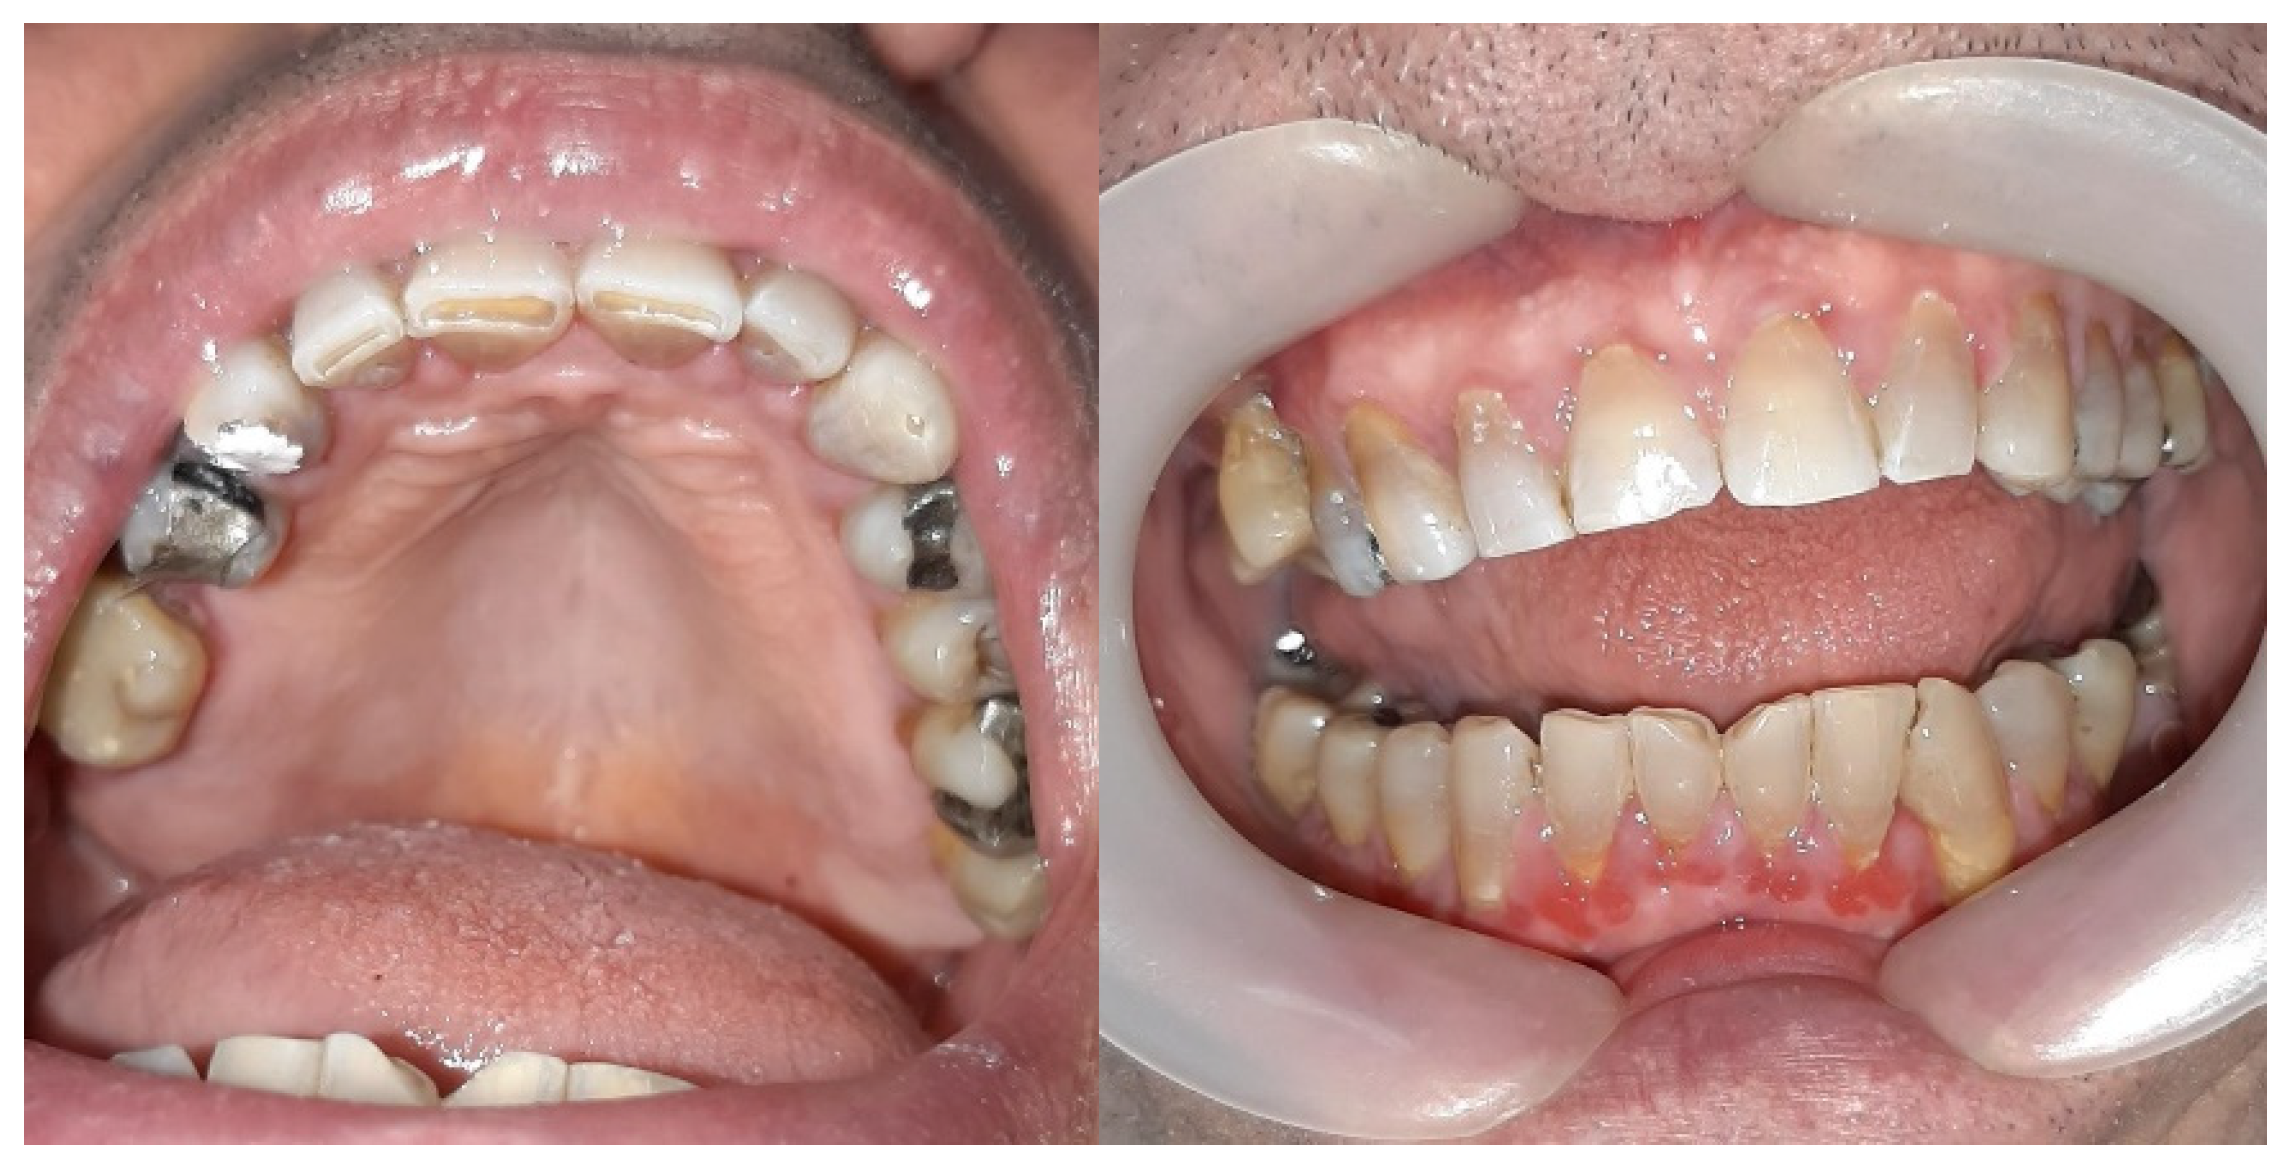

A clinical examination revealed significant gingival overgrowth around all present teeth, affecting both the vestibular and oral sides. The enlarged gums bled easily on probing and were covered with erosions and white thick plaque, which was hyperkeratotic in appearance. The patient was found to have significant supra- and subgingival tooth deposits (Figure 1). Swabs for bacteria and fungi were negative.

Six months after gingivectomy Zelboraf dose was reduced to 720 mg twice daily, and Cotellic (cobimetinib) was introduced at 60 mg per day, which resulted in a decrease in gingival enlargement (Figure 5).

Figure 1. Gingival overgrowth during the first visit. The enlarged gums were covered with erosions and a thick, white plaque which appeared to be hyperkeratotic.

Figure 5. Photographs of the patient’s mouth after Cotellic was introduced. Inflamed but not hyperplastic gingiva was noted on examination.